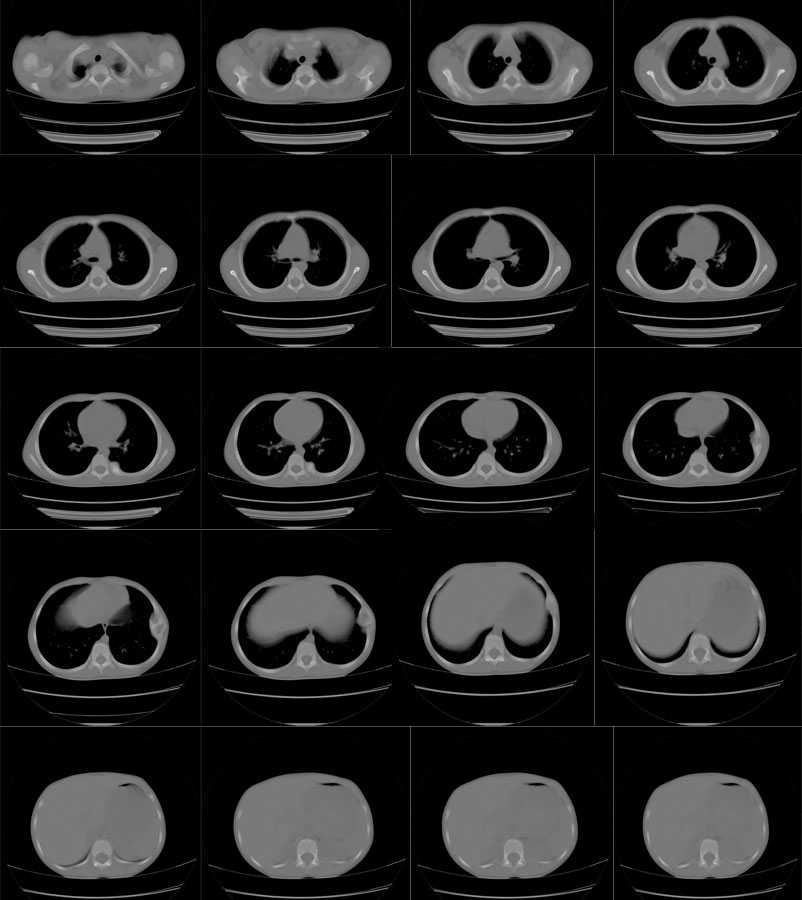

标题: PED2876:肋骨多发病变,考虑骨纤,请大家高见。

男,7岁,左侧胸部突出,有时痛,无其它症状

支持左第八肋腋侧骨纤。